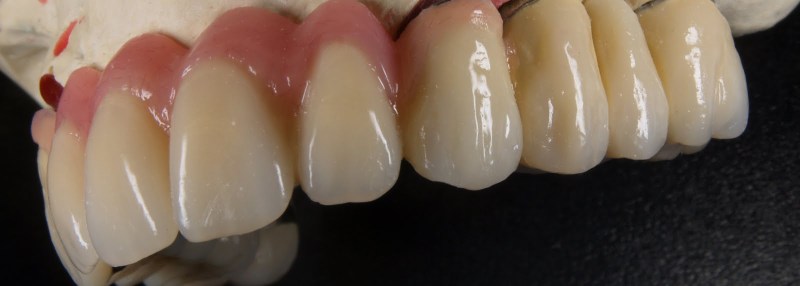

Keramik auf Metall